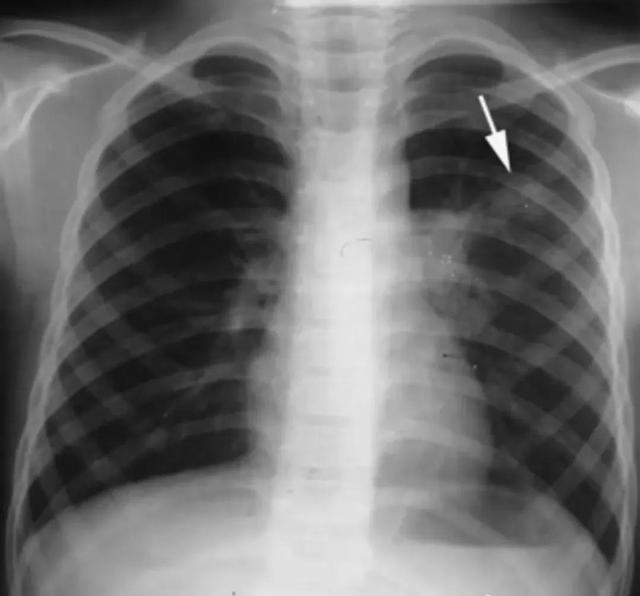

肺结核的分型诊断标准,肺结核的分型及影像学表现

原发综合征 胸部正位片,左上肺可见斑片状模糊影,与左肺门增大软组织影相连接,呈典型“哑铃状”